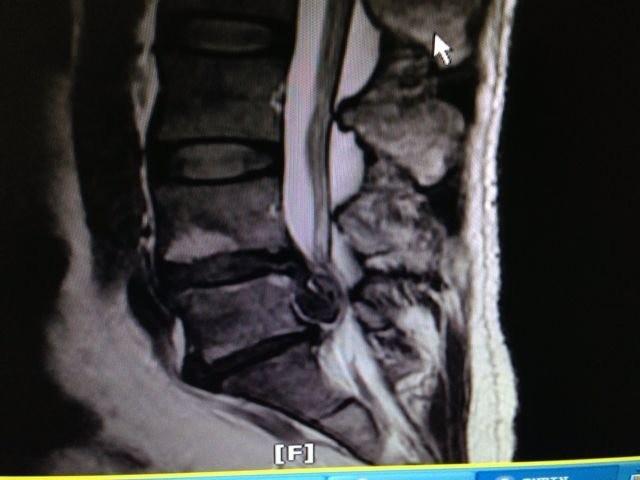

患者陈先生,44岁,3月前出现右侧腰臀部及下肢轻微疼痛,一周前患者感觉疼痛加剧,呈电击样,弯腰或行走后加重,后致不能行走,且伴大便无力。于是来我院疼痛科就诊,被许峰副主任诊断为“腰椎间盘突出症”。核磁共振检查发现髓核突出物巨大,像“黑眼珠”,脱出椎管内,神经根明显受压。次日,许峰副主任给患者实施了“椎间孔镜下腰椎间盘髓核摘除术”,术中铗出的突出物竟然长约10cm,重约10g。术后患者腰腿疼痛立刻消失,两天后排便正常,一周后出院。